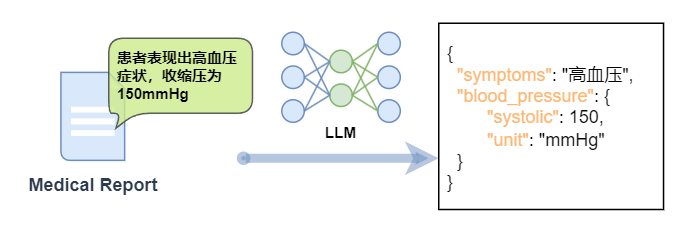

举个医疗领域的例子🌡️:当医生面对“患者表现出高血压症状,收缩压为 150mmHg”这样的医疗报告时,需要将其转换成包含症状、血压读数等关键信息的 JSON 格式。如果让没经过微调的通用模型来做,可能会漏信息、格式出错,甚至误解专业术语。但经过微调的大模型,就能像“专业书记员”一样,精准搞定!

微调带来的“超能力”,每一项都很能打!

1.精确信息提取:火眼金睛揪出关键数据📝

微调就像给模型装上“信息探测器”,再也不怕重要信息“躲猫猫”!

2.上下文理解:前后逻辑全吃透🔍

自然语言里,一句话的意思往往和上下文紧密相关。微调后的模型能读懂这些隐藏的逻辑,转换信息时更贴合实际场景,再也不是断章取义的憨憨啦!

3.格式严格把关:强迫症患者的福音📄

JSON 等结构化文本就像“规范考场”,格式错误直接“不及格”。微调能让模型严格遵守格式要求,生成的文本就像“印刷体”一样工整!

4.术语专业处理:秒变领域“本地人”⚕️

医疗领域的“收缩压”“舒张压”,金融领域的“市盈率”“复利”等,这些专业术语就像领域的“方言”。微调让模型熟悉“行业黑话”,交流起来毫无障碍,再也不会闹“术语笑话”啦!